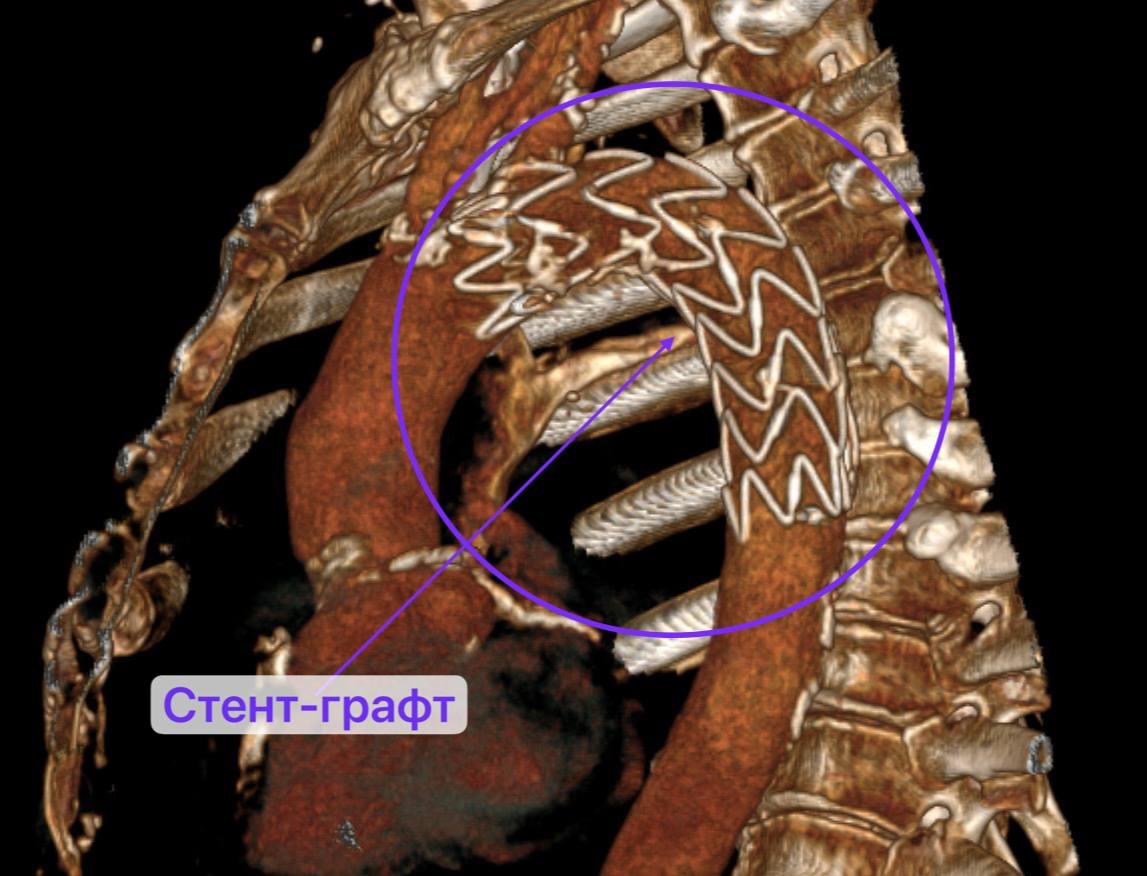

«Оперировать легкое было опасно, аневризма, как бомба, могла разорваться в любой момент. Поэтому сначала за пациента взялись рентген-хирурги – установили стент-графт (устройство для укрепления стенок аорты), чтобы предотвратить разрыв аневризмы. Стент-графт подбирается индивидуально под каждого пациента. После чего мужчину наблюдали и лечили в отделении сосудистой хирургии. К моменту перевода в торакальное отделение №1 хирурги получили результаты биопсии», — поделились специалисты.